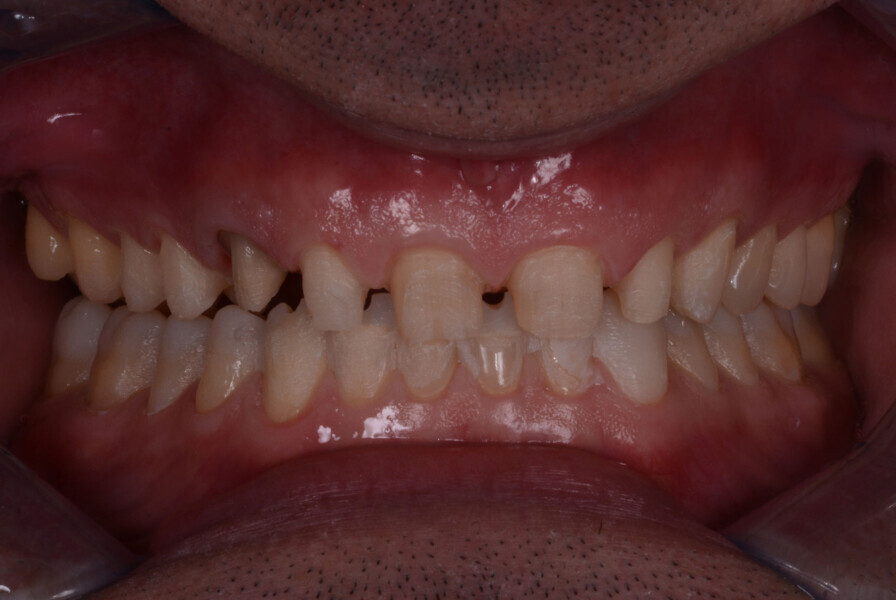

Fig. 1: Intraoral photograph prior to treatment, frontal view.

Fig. 7: Two years later, prior to treatment (2017).